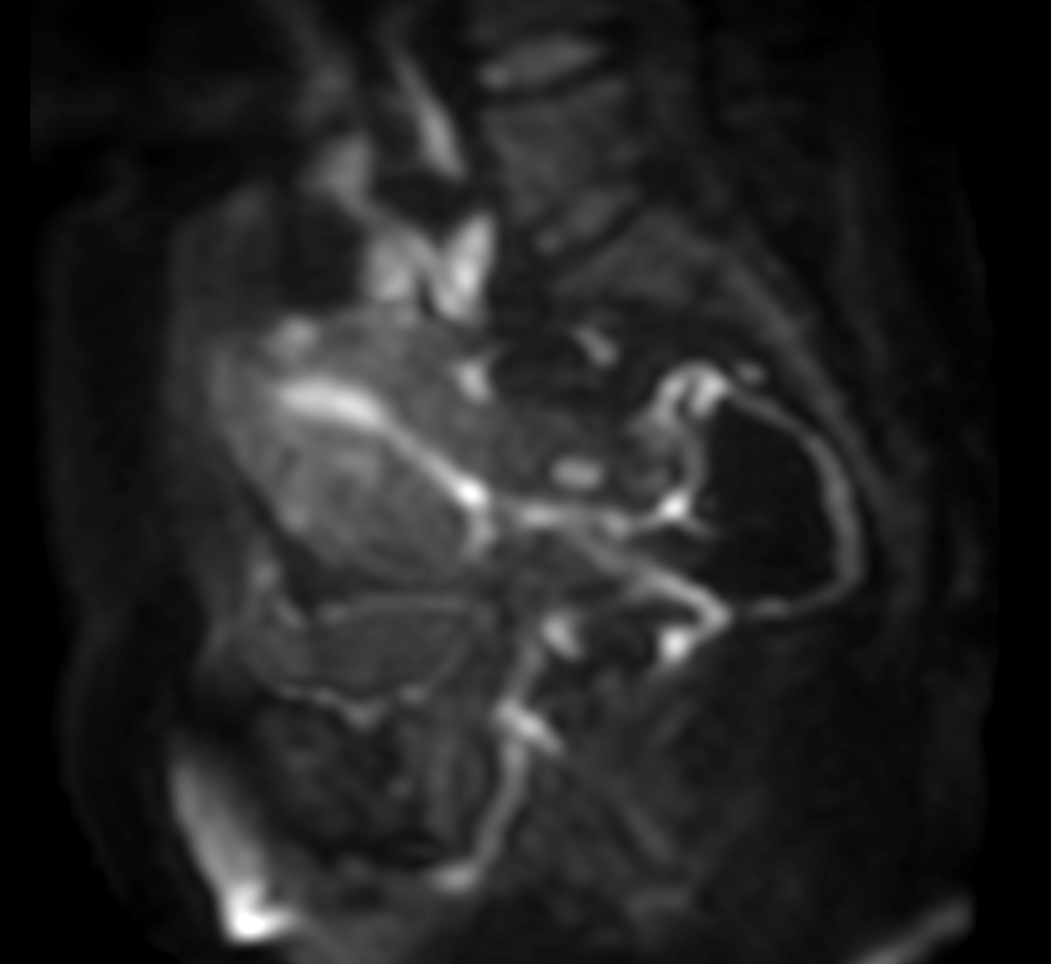

Coronal mDIXON XD - T1w FFE plus gado (Water only)